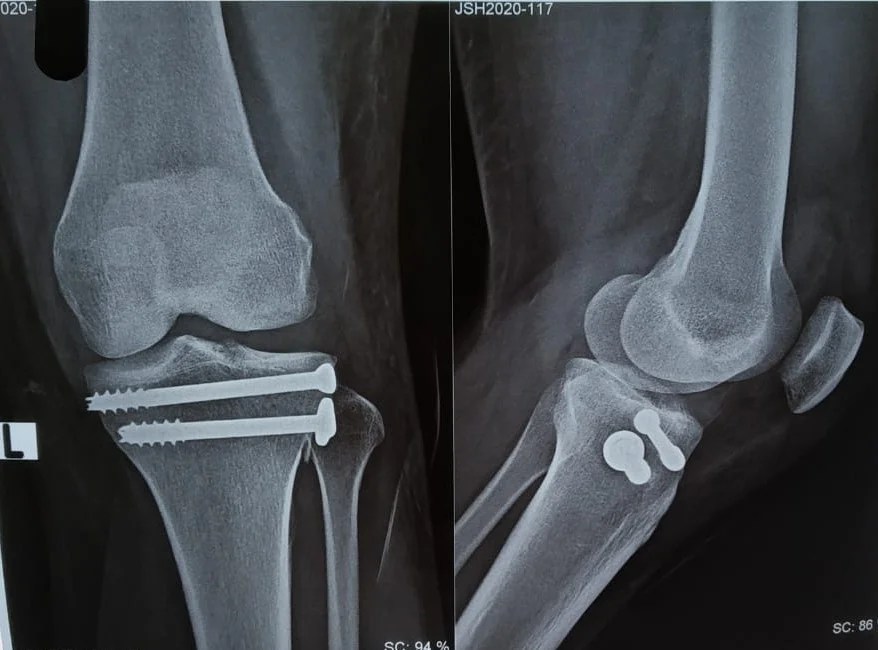

From www.researchgate.net

Total knee replacement after removing proximal tibial nail screws.... Download Scientific Diagram Screw Removal From Tibia What to generally expect during surgery & recovery. Hello, i broke my tibia in april 2018 and had surgery to insert a plate and 9 screws. I have pain walking every day all day. If a tendon is in constant contact with a plate, screw, or pin, the. Knee problems come when you have alignment problems in. Are you having. Screw Removal From Tibia.